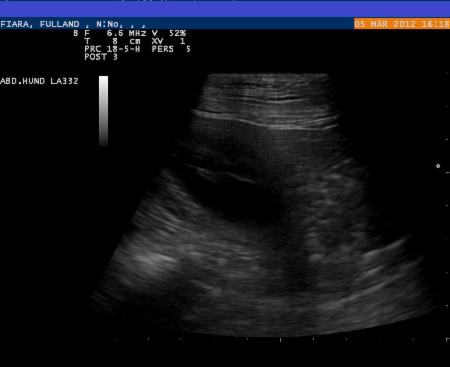

Wir waren am 05.03.2012 beim Ultraschall:

Fiara ist tragend !!!

Und hier die Beweise: Die ersten Fotos der Babys, die Ultraschallbilder !!!

05.03.2012